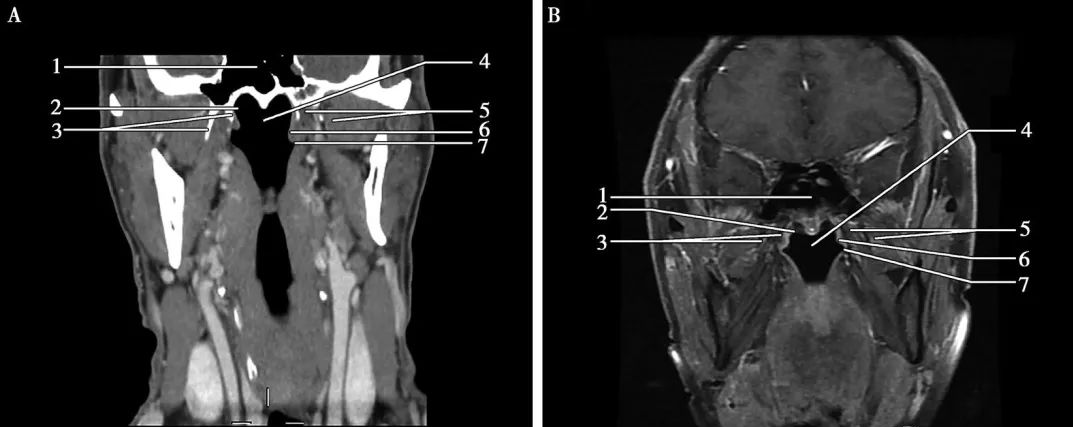

▲冠狀面(miàn)-鼻咽層面(miàn) A.CT;B.MRI

鼻咽癌表現爲鼻咽部軟組織腫塊,病竈大小不等,早期腫塊不明顯,僅表現爲咽隐窩變淺,腭帆提肌腫脹,晚期表現爲突出鼻咽腔的腫塊,大者可占滿鼻咽腔,形态不規則,可侵犯鄰近結構,沿顱底孔道(dào)蔓延至顱内。影像學(xué)檢查對(duì)确定腫瘤侵犯範圍及與周圍重要結構的關系十分關鍵。在區别腫瘤和軟組織,評估淋巴結轉移,觀察腫瘤沿神經(jīng)擴散和骨髓受累方面(miàn),增強MRI優于CT掃描。CT掃描可以更好(hǎo)地顯示早期顱底骨質破壞和其他的骨質破壞征象。

CT表現:鼻咽癌局限在黏膜間隙時(shí),CT表現爲鼻咽腔兩(liǎng)側不對(duì)稱,局部黏膜增厚,一側咽隐窩變淺或消失,腭帆提肌、腭帆張肌腫脹,脂肪間隙消失。可引起(qǐ)周圍結構的侵犯:向(xiàng)前侵犯鼻腔,達翼腭窩,向(xiàng)兩(liǎng)側侵犯咽旁間隙,向(xiàng)後(hòu)侵犯咽後(hòu)間隙以及椎前肌,向(xiàng)下侵犯口咽軟腭和扁桃體,向(xiàng)上侵犯斜坡及顱底骨質,通過(guò)顱底孔道(dào)進(jìn)入顱内。鼻咽癌常并發(fā)頸部淋巴結腫大。CT增強掃描,腫塊輕度強化,邊界不清(下圖)。

MRI表現:MRI顯示腫瘤範圍、周圍結構侵犯以及頸部淋巴結腫大與CT基本相同,因MRI軟組織分辨率較CT高,所以MRI能(néng)更早的發(fā)現病變,并準确地顯示病變部位、大小、範圍及浸潤深度。T1WI上腫塊相對(duì)于肌肉呈低-等混雜信号,T2WI呈較高信号,增強後(hòu)輕度強化(下圖)。